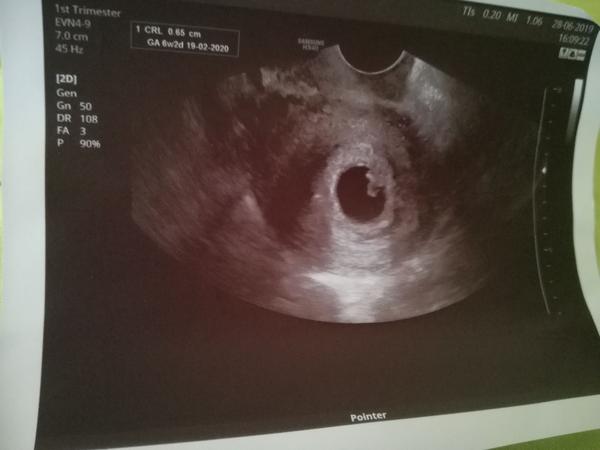

@maminka2020 Tak já měla dva týdny zpět úplně stejný obrázek (prázdný gestační váček - 5. týden). Objednali mě moc brzy a dva týdny jsem se zbytečně stresovala. Min. týden jsem byla na kontrolním ultrazvuku a bylo tam krásně vidět i srdíčko. Prostě jsem měla ovulaci později. Držím pěsti, ať to dobře dopadne.

@maminka2020 Mám z 6+2